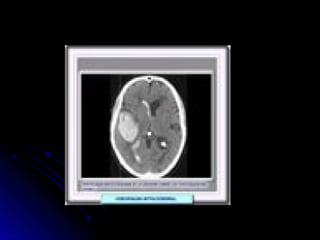

• 34.

Ubicación de laslesiones en TAC-RNM